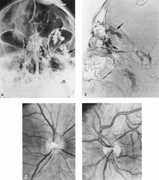

Fig. 7. Supratentorial arteriovenous malformation in a 28-year-old woman with a history of focal motor seizures for many years and a recent subarachnoid hemorrhage. A: Lateral projection carotid arteriogram demonstrating a huge deep hemispheral arteriovenous malformation. B: Frontal projection. C: Fundus photograph showing anomalous tortuous vasculature in each eye. No retinal arteriovenous shunt was detectable.

Fig. 8. Multiple supratentorial arteriovenous malformations (AVMs). A: Lateral projection of left carotid arteriogram shows dilated afferent artery (solid arrow) feeding the right hemispheric parietal AVM (open arrow). B: Right carotid injection fills a second, more posteriorly located, parietooccipital AVM (open arrow), which drains immediately to markedly dilated cortical veins (curved arrow).

Fig. 9. Carotid arteriogram of an occipital lobe arteriovenous malformation (AVM). Lateral (A) and frontal (B) projections demonstrating a small occipital AVM (arrow). The patient was a 23-year-old woman who presented with severe apoplectic unilateral headache, total left homonymous hemianopia, and mild nuchal rigidity. Despite xanthochromic cerebrospinal fluid, she was initially diagnosed elsewhere as having migraine. An AVM was successfully resected, and a small occipital lobe hematoma was removed.